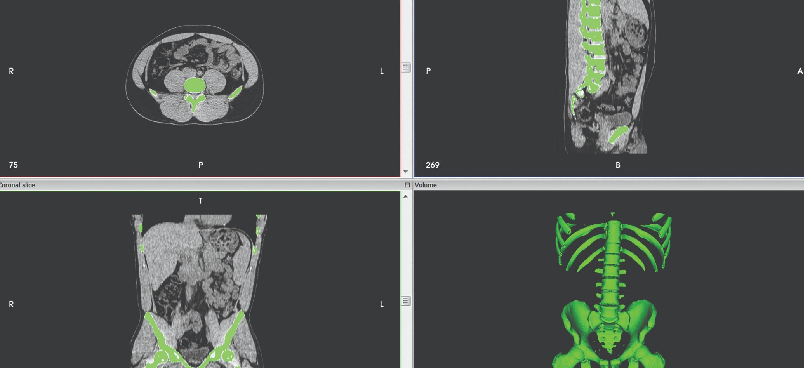

Data segmentation for medical 3D printing application guide

The challenge in developing these models is isolating the specific anatomy of interest from the medical imaging data, a process called segmentation. Download this how-to guide covering segmentation techniques and best practices to create accurate, realistic medical models.